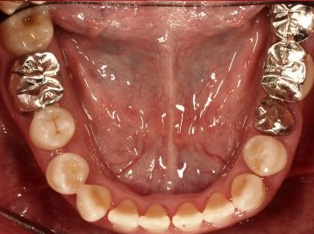

治療前

治療終了前

下顎が上顎より前に出ている状態です。お顔つきも、下顎の先(オトガイ)が前に出ているような横顔になる場合が多いです。前歯が咬んでいないことが多く、奥歯への負担が大きい状態になります。そのままのかみ合わせを続けてしまうと、奥歯がかけたり、割れたりするリスクが高まります。歯列矯正では奥歯の位置をコントロールし、前歯のかみ合わせを作る治療方針を立てます。ごく稀に、歯列矯正ではかみ合わせを作れない場合もあり、その場合は外科矯正という手段を用いて矯正治療をしなければいけません。受け口は、遺伝性が強いとも言われておりますので、そういった情報も考慮し、治療を進めていくことが大切です。